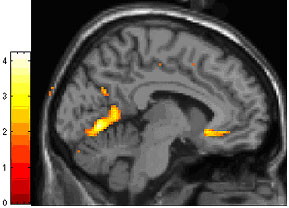

Previous findings7 of lower-than-normal grey matter matter - neurons and their connections - in the regulator hub, called the anterior cingulate cortex (ACC), hinted that this might affect the way the brain works in BPD.

Suspecting that this functional impairment mirrors structural differences — as has been found in depression — the researchers next used anatomical MRI to compare grey matter in the same patients and healthy controls. Consistent with the fMRI results and the earlier findings, grey matter density was increased in parts of the amygdala and decreased in parts of the ACC, in BPD patients relative to controls. This suggested an abnormality in the number or architecture of neurons in these key components of the emotion-regulating circuit, which other evidence links to impaired functioning of the serotonin chemical messenger system.

Patients with borderline personality disorder had significantly lower density of grey matter, the brain's working tissue, in the anterior cigulate cortex, an area (yellow, at right) that regulates the brain's fear hub (below). MRI scan data shows the difference between patients and controls.